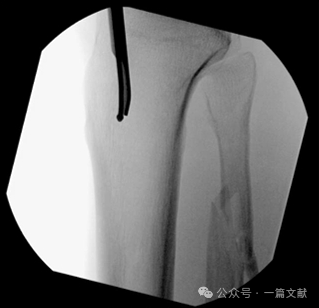

图1,髓内钉开口:(A) 在正位(AP)图上,导针位于胫骨外侧髁间棘的内侧。(B) 在侧位上,导针位于胫骨关节面的前缘,以避免损伤关节面或半月板,同时防止远端扩髓对胫骨结节和髌腱的影响。